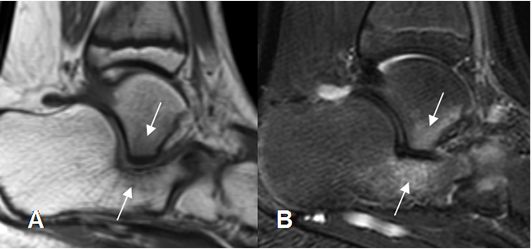

Fig 139. Coalición del tarso.

A: RM sagital en T1 y B: RM sagital en STIR. Coalición talocalcánea cartilaginosa, con edema óseo asociado.